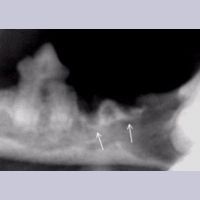

Image 7.17. 뢴트겐 사진

Image 7.18. Flap exposure for extraction

(적출을 위한 잇몸 절개?)

송곳니의 resorption 내부